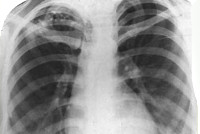

Основную информацию о форме туберкулеза дает рентгенография легких, однако рентгенологическая картина может быть различной в зависимости от фазы и длительности процесса. При свежем очаговом туберкулезе обычно определяется 1-2 крупных очага и несколько средних или мелких; тени слабоконтурирующие, малоинтенсивные, округлой формы. Хронический очаговый туберкулез рентгенологически проявляется наличием плотных фокусов с очагами обызвествления и фиброзных тяжей; тени средней и высокой интенсивности, обычно малого и среднего размера.